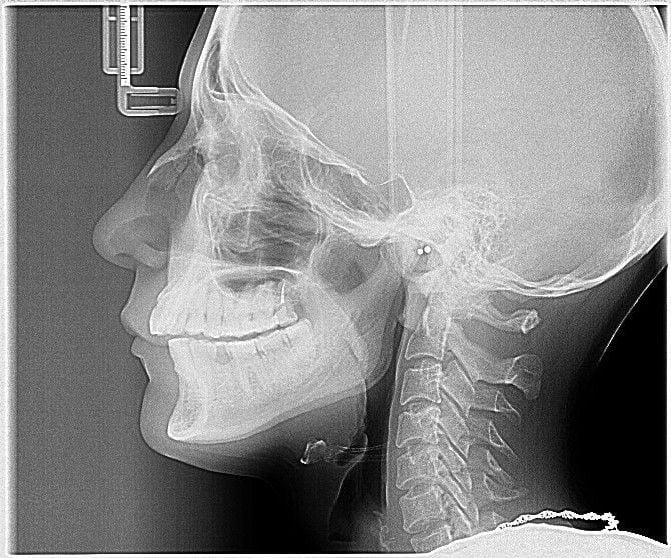

Начальным этапом диагностики артроза челюсти являются осмотр и анализ жалоб пациента, выявление асимметрии лица, пальпация жевательных мышц. Для уточнения диагноза, определения локализации и степени поражения хрящевых структур челюстного сустава проводится инструментальное обследование.

Инструментальная диагностика артроза челюсти включает проведение:

- рентгенографии;

- компьютерной томографии;

- магнитно-резонансной томографии.

Все эти методы позволяют обнаружить характерные симптомы артроза: истончение хрящевой прослойки, эрозии, трещины и другие дефекты на поверхности хряща, разрастания остеофитов, деформацию суставных структур.

Чаще всего диагноз ставят на основании результатов рентгенографии. Однако этот метод не позволяет оценить состояние и выявить поражение близлежащих мягких тканей. Поэтому при необходимости дополнительно может проводиться КТ или МРТ.

Для определения стадии развития заболевания, его локализации чаще других используется рентгенография. Рентгеновский снимок позволяет увидеть возникшие деформации, разрастания костей, изменения их формы. Реже применяются КТ, электромиография, контрастная рентгенография или брекеты (ортодонтические скобы).

Диагноз ставится на основании данных, полученных в ходе объективного осмотра, пальпации, аускультации и рентгенографии. Последняя является основным методом при диагностировании артроза ВНЧС. Благодаря ей заметны первые патологические изменения в суставе. Более точную информацию о его состоянии даст томография.